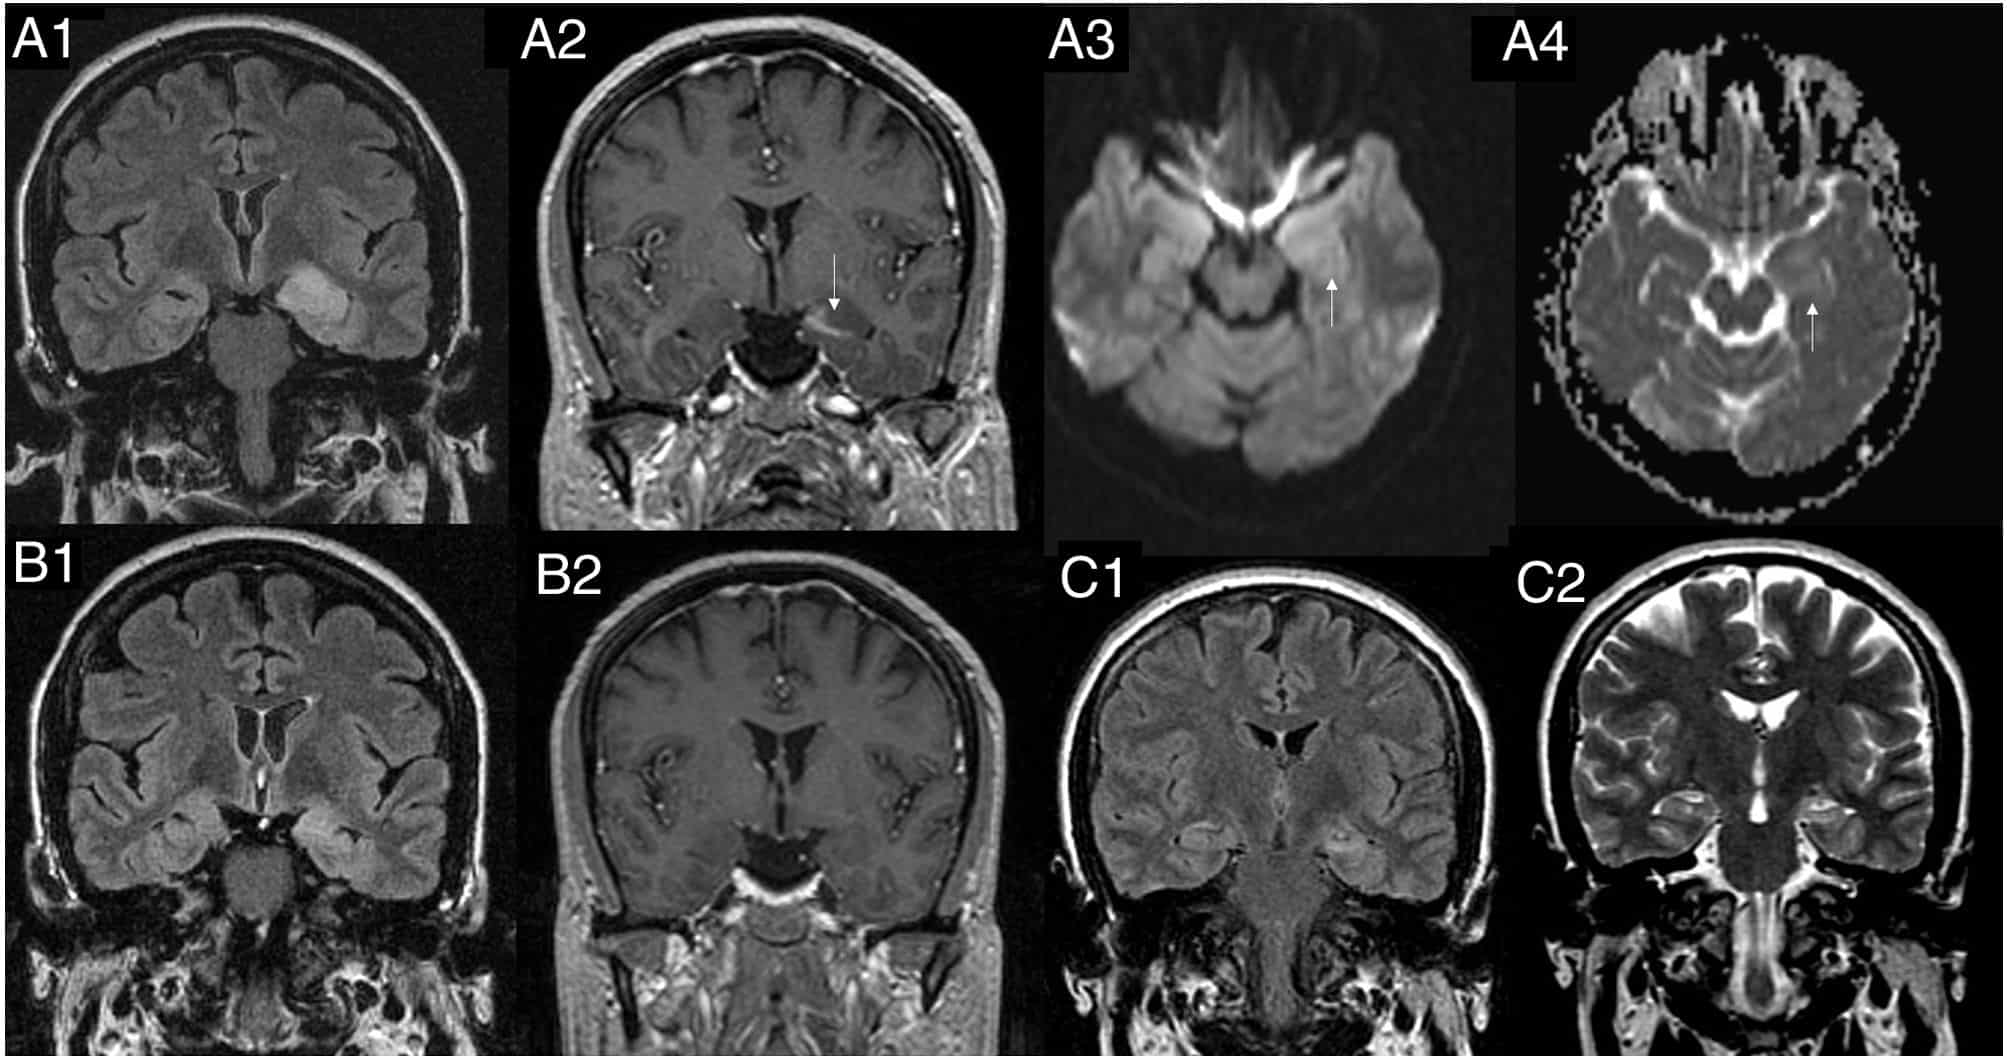

Neuroimagen en Epilepsia: RM, PET, SPECT y Nuevas Herramientas

La neuroimagen es hoy un pilar fundamental en el diagnóstico, la localización y el manejo de la epilepsia, especialmente en pacientes con epilepsia focal farmacorresistente evaluados para cirugía o neuromodulación. En […]